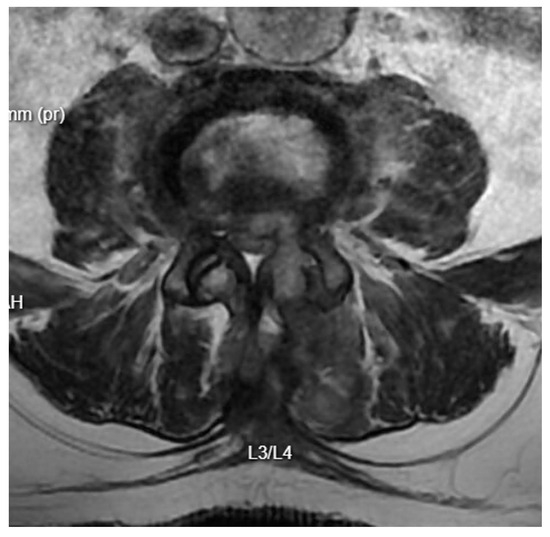

Further Intervention: Another MRI confirmed that despite extensive decompression, significant narrowing persisted at the operated level, with a markedly increased T2 signal in the disc space (Figure 7). A subsequent endoscopic transforaminal approach was employed. Inflammatory disc material and granulation tissue from the spinal canal were removed. Post-operative MRI showed a satisfactory degree of decompression of the canal. The patient was mobilized and transferred to the nephrology department due to further deterioration of renal function.

Figure 7. T2 axial MRI image at the L4/L5 level following previous open surgical treatment.